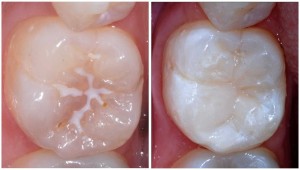

Fissure Sealant

Fissures are natural grooves/ valley shapes found on the biting surfaces of the back teeth. Permanant and baby teeth. Some people have ‘deep’ fissures meaning food/ bacteria gets stuck with greater ease causing a higher risk of decay. By ‘sealing’ these fissures we add a layer of material so food/debris does not accumulate preventing decay.